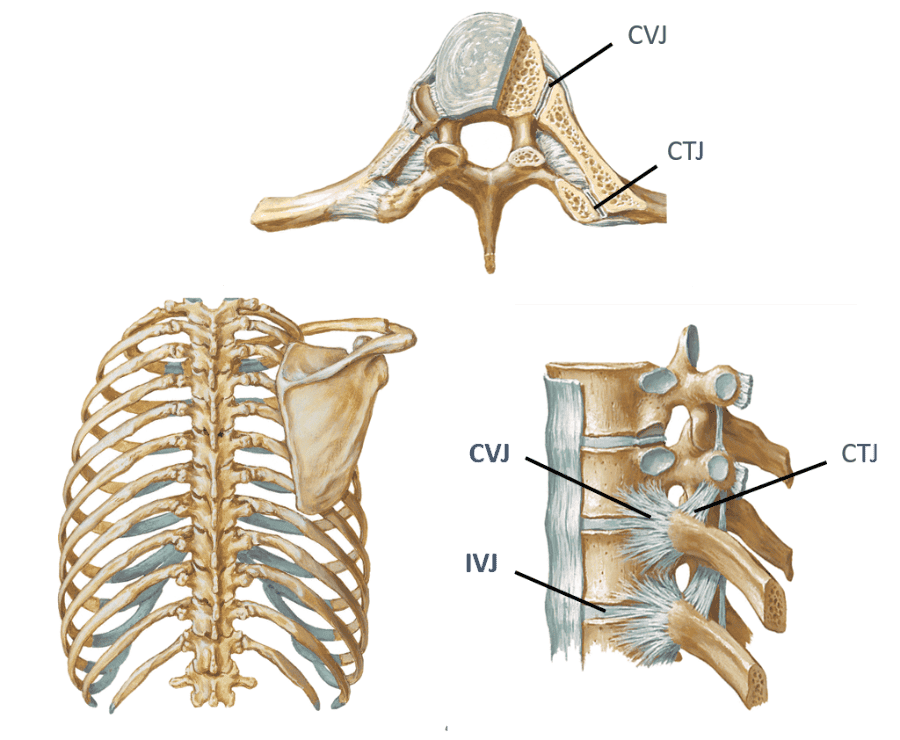

look at picture

Identify the landmarks thoracic vertebrae 1-12

Spinous process

(SP)?

Transverse process (TP)?

Costal facets along vertebral

bodies (CF)?

Transverse costal facets (TCF)?

study picture

look at picture

what do the costal facets have along the vertebral bodies, except for where?

what is the transverse costal facets along? except for where?

Costal facets along vertebral bodies (CF)...Pairs of inferior (ICF) and superior (SCF) on vertebrae except lower 4 thoracic vertebrae

Transverse costal facets (TCF)..along transverse processes except lower 2 thoracic vertebrae...notice how T12 in pic does have a transverse costal facet

in theory, typical ribs should articulate with what?

2 vertebrae

describe what these joints articulate with?

- Costovertebral joints (CVJ)

- Costotranservse joints (CTJ)

- Intervertebral joints (IVJ) of the thoracic spine

- Costovertebral joints (CVJ)...rib articulation with vertebrae body

- Costotranservse joints (CTJ)...rib articulation with transverse process of vertebrae

- Intervertebral joints (IVJ) of the thoracic spine...Disc and facets